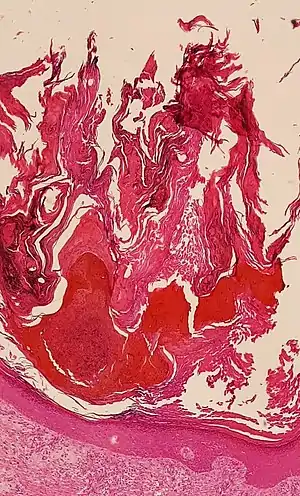

| Micrograph showing prominent hyperkeratosis in skin without atypia. H&E stain. | |